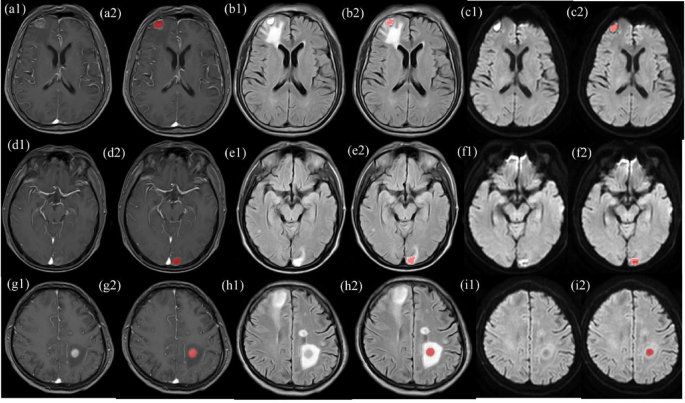

The images were exported into Digital Imaging and Communications in Medicine format. All cases in the training cohort were used to train the predictive models, whereas cases in the test cohorts were used to independently evaluate model performance. Before analyses, in ITK-SNAP (version 3.8.0, www.itksnap.org) software, the entire volume of the region of interest (ROI) was manually contoured slice by slice along the boundaries of the tumor on T1CE, T2-FLAIR, and DWI images, by a radiologist with 5 years of diagnostic experience15. The segmentation process was supervised by a senior radiologist with 10 years of experience, to ensure the accuracy of the delineations. To ensure that the evaluation process was as unbiased as possible, and that the results were representative, the two assessors were fully blinded to the patients’ pathological diagnoses. Figure 2(a1–2, b1–2, c1–2, d1–2, e1–2, f1–2, g1–2, h1–2, i1–2) shows the ROI ranges for patients with SCLC, AD, and NAD with BMs.

Delineation of ROIs in T1-weighted imaging (T1WI) (a1–2, d1–2, g1–2), T2-fluid-attenuated inversion recovery (T2-FLAIR) (b = 800) (b1–2, e1–2, h1–2), and diffusion-weighted imaging (DWI) (c1–2, f1–2, i1–2). a1–2, b1–2, c1–2: man, 66 years old, with BMs in SCLC. a1, b1, and c1 represent the original lesions, and a2, b2, and c2 show the lesions after ROI delineation. d1–2, e1–2, f1–2: man, 45 years old, with BMs in AD. d1, e1, and f1 represent the original lesions, and d2, e2, and f2 depict the lesions after ROI delineation. g1–2, h1–2, i1–2: man, 49 years old, with BMs in NAD. g1, h1, and i1 represent the original lesions, and g2, h2, and i2 display the lesions after ROI delineation.